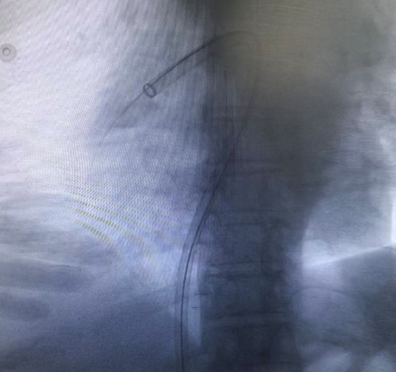

右侧股静脉置管,送⼊ 5F Pigtail 造影导管⾏双肺动脉造影。右下肺动脉主干及多肺段均见充盈缺损

,部分分支闭塞。左肺主干及多肺段均见充盈缺损。

术前造影